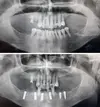

Periimplantitis

Peri-İmplant Mukozitis

Implant tedavisi